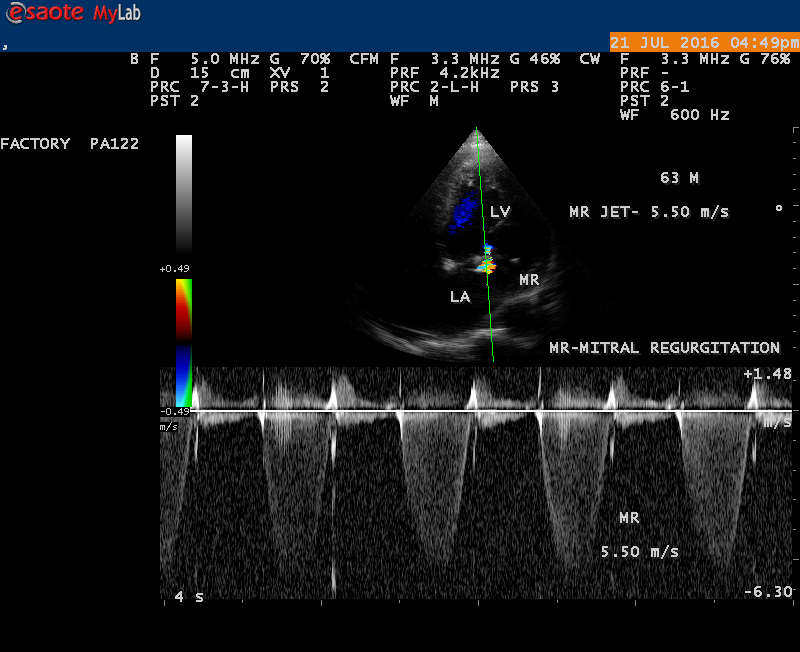

Echocardiography is the only noninvasive method available for direct visualization of endocarditis-induced lesions. Echocardiographic finding in patients with infective endocarditis was initially observed by Dillon [25] and Spangler, et al [26]. The vegetation will grow in size, either as a sessile clump or a highly mobile and even pedunculated mass with the potential for embolization. Vegetation can be detected when the valve attached mass reach a diameter of ≥ 2 to 3 mm [27]. In both children and adults, 2-D echocardiography is usually the more sensitive technique with sensitivity in children up to 80% [28]. Valvular dysfunction due to tissue disruption or large obstructing vegetation can be visualized and quantitated by echocardiogram with Doppler [29]. The detection of a large eccentric jet adhering, swirling, and reaching the posterior wall of the LA is in favour of significant MR (mitral regurgitation) as shown in Figures 22, 24 and 25.

The most common and direct evidence of infective endocarditis is the vegetation and it begins as a microscopic focus of infection and gradually grows into a conspicuous mass. It is typically an irregularly shaped, highly mobile, echogenic mass attached to the free edge of a valve leaflet ( most commonly at the coaptation line) and tends to develop on the ‘upstream’ side of the valve leaflets ( ie, the ventricular side of aortic valve and the atrial side of mitral and tricuspid valves. They may be seesile or pedunculated, but usually has an oscillating or fluttering motion, a typical feature of most vegetations. Vegetation move with the leaflet in a more chaotic (‘oscillating’) manner and it may prolapse through the valve into the LV (left ventricle) as it opens as shown in Figures 3, 4 and 16 and into LA (left atrium) as it closing (Figure 5 and 6) . The mass of vegetation is typically homogeneous with echogenicity similar to that of the myocardium. The infectious process often alter the valvular structure and function. Extensive involvement of the leaflet may result in chordal rupture, leading to severe regurgitation as shown in Figure 21 . Direct and typical signs of RMCT (ruptured mitral chordate tendineae) were chain-flail or whiplash-like changes and had an incidence of 86.7%, causing severe regurgitation and mitral chordal rupture is the leading cause of flail mitral leaflet[30]. A large vegetation may obstruct the valve orifice as shown in Figure 1 and 2 , sometimes termed as “obstructive-type bacterial endocarditis” and producing a functional valve stenosis ( Ping-Pong mitral stenosis [31]) similar to left atrial myxoma as shown in Figure 29.

The shape and size of vegetation are quite variable and mostly it is polypoid [32]. The typical vegetation is a ‘sessile’ or ‘ pedunculating’ valve – attached mass. A ‘sessile’ vegetation had to be completely attached to the valve as shown in Figures 34 and 35 in a 63- year old male, in which a large vegetation is attached to the atrial side of anterior mitral leaflet [33-Figure 13.3-A], producing severe mitral regurgitation as shown in Figure 36 and a mobile vegetation showed a pedunculating part prolapsing into the ventricle as shown in Figure 3 and 4 or atrium as shown in Figure 5 [33-Figure 13.1] in a 10-year old female child. A vegetation was considered as ‘definite’ when shaggy echoes in the M-mode study as shown in Figure 20 . and a corresponding mass without restricted valve motion in the two-dimensional echocardiogram were found as shown in Figure 16 and 30 [33-Figure 13.7]. The vegetation vary in size, often being just a few mm and sometimes reaching to 2-3 cm. A vegetation must be atleast 3 to 6 mm in size to be reliably seen. The mean size of vegetation was 0.6 mm (range 3 to 28) and vegetation > 10 mm in diameter was defined as ‘large’ and those ≤ 10 mm in diameter was defined as ‘small’ and ≥ 15 mm is ‘very large’. Vegetations resulting from fungal infections (candida, aspergillus) are usually much bigger than bacterial vegetations and can be so big to be mistaken for a cardiac tumor. The large vegetations are at increased risk for embolic complications [34], especially on the anterior leaflet of the mitral valve with mobility [35]. A vegetation size of 3.2 x 4.4 cm is called as ‘giant vegetation’ on the mitral valve with a fibrillary appearance of the mass [36- Figure 3] as shown in Figure 1 is an important predictor of embolic phenomena in patients with infective endocarditis causing severe mitral regurgitation as ‘Duck’ shaped jets (Figures 24 and 25 ), disorganized (Figure 21) and sometimes the regurigitant jet splits into two components as one into LA and the second one into LV simultaneously as a bileaflet jets (Figure 10 ) similar to bileaflet structure of AML with vegetation masses (Figure 9 ) . The size of the largest vegetation reported on the mitral valve in the literature in patients with bacterial endocarditis is 7x4 cm[37]. In a study of Nunes, et al[38], vegetation size >13 mm was the only independent predictor of mortality, but some studies [39],[40] did not had an increased embolic risk in patients with vegetation focused only on its presence and size and not on their location. Embolic complications may occur in infective endocarditis(20.6%)and were not more prevalent in the groups with large vegetations [41]. However, Wong, et al [42] found an increased need for surgery in patients with a large vegetation (>10 mm).

The anatomic disruption of a portion of the mitral valve apparatus dueto the underlying rheumatic valvulitis with predisposing infective endocarditis which form a vegetation , resulting an eccentric regurgitation jet with orientation opposite in direction of the leaflet having the anatomic defect such as ‘flail’. In the presence of ‘flail leaflet’, the mitral regurgitant spectral signal may have an atypical appearance and the flail portion oscillate in the spectral signal of regurgitant flow stream to produce a ‘tiger stripe’ appearance as shown in Figure 27. associated with ‘whistling’ sound on auscultation[33-Figure 11.85]. The mitral regurgitation (flail MR) jet is chaotic as shown in Figure 26, highly eccentric (Figure 22) and disorganized with one component behind the anterior mitral leaflet and the second component directed towards posterior immediately as in Figure 21 [33- Figure 11.79].

The severity of eccentric MR is underestimated because of coanda effect. If the regurgitant jet area fills < 20> 40% indicate severe regurgitation. The vena contracta ( the neck or narrowest portion of the jet), typically imaged perpendicular to the commissural line in parasternal long axis and apical four chamber views is well defined in both central and eccentric jets, but not in chaotic, disorganized jets due to flail leaflets. Its width < 3> 7 mm defines severe MR and a mean value of > 8mm indicates severe functional MR. The flow convergence method based on PISA (proximal isovelocity surface area) may not applicant for eccentric and multiple jets or complex and elliptical regurgitant orifices to assess the severity of mitral regurgitation.. The adaptation of LV to the increased volume overload is reflected by LV dimensions and ejection fraction.. In chronic compensated phase, the forward stoke volume is maintained through an increase in LV ejection fraction >65% and the patient could be asymptomatic. In chronic decompensated phase of MR, the forward stroke volume decreases and the LA pressure increase significantly. The patient may be still asymptomatic and the LV ejection fraction may be in the low normal range despite the presence of significant muscle dysfunction. The contractile function decreases silently and become irreversible. In the current guidelines, surgery is recommended in asymptomatic patients with severe organic MR when the LV ejection fraction is ≤ 60%. However, in acute stage, the LV ejection fraction increases in response to the increased preload. The end-systolic diameter is less preload dependent than the ejection fraction and it may be more appropriate to monitor the global LV function. The end-systolic diameter > 45 mm also indicate the need for mitral valve surgery [43]. In this child, the LVESD (end-systolic diameter) is 30.7 mm and the ejection fraction (EF) is 66% as shown in Figure 19. New parameters are currently available for a better assessment of LV function. A systolic tissue Doppler velocity measured at the lateral annulus <10>40-50mm) may predict the onset of atrial fibrillation and poor prognosis in patients with organic MR[48]. The excess regurgitant blood entering in the LA may induce acutely or chronically a progressive rise in pulmonary pressure and the presence of TR (tricuspid regurgitation) as shown in Figures 26 and 28 permits the estimate of systolic pulmonary arterial pressure and mitral valve surgery is recommended when it is > 50 mmHg at rest and LA reverse remodeling may occur after surgery. The severe TR may cause a decrease in hepatic vein systolic velocity and systolic flow reversal may occur as shown in Figure 32 and its sensitivity is 80% [49]. The TR (tricuspid regurgitation) jet velocity in this child is 4.03 m/s as shown in Figure 28 which corresponds to a systolic pulmonary artery pressure of 65 mmHg.